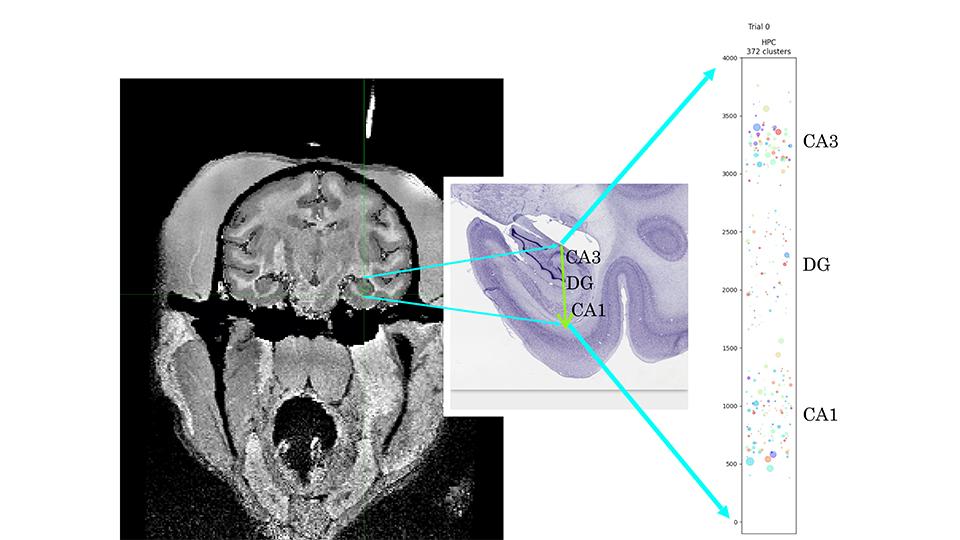

Neuroscientists have traditionally characterized neuronal response selectivity to reveal how the brain represents emotional states. For instance, neurons in basolateral amygdala (BLA) respond selectivity to positive and negative valence. However, emotions involve more than valence, and it is unclear how BLA encodes all relevant variables. If each neuron encodes one variable, then readouts of different variables would not interfere with each other, and readouts would also generalize across conditions. But can these computational properties be realized if neurons lack specialization? We tested this by presenting stimuli to mice that elicited two responses: tremble and ingress into a burrow, reflecting fear and flight to safety.  BLA inactivation eliminated differential responses to aversive and neutral stimuli without eliminating responses themselves, suggesting BLA signals valence, not motor commands. However, two-photon imaging revealed that neurons exhibit mixed selectivity for stimulus identity, valence, tremble and/or ingress. Despite this, BLA population activity represented valence, tremble and safety within low-dimensional geometries, reflecting linear mixed selectivity and enabling generalization across conditions. Further, tremble and valence coding directions were orthogonal, eliminating interference between readouts. Thus BLA can achieve specialized readouts of variables describing emotional states with particular representational geometries, not requiring neurons with specialized selectivity.